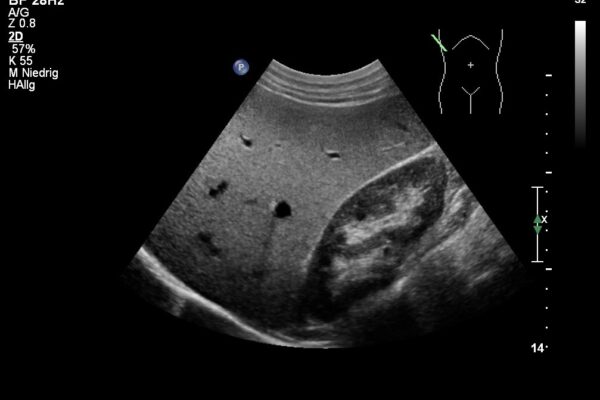

Im Ultraschall der Bauchhöhle beurteilt der Arzt die Grösse, die Struktur und die Lage der Bauchorgane und Gefässe.

In den letzten Jahren wurde die Ultraschalluntersuchung bei Kindern das führende bildgebende Verfahren. Vom Säugling bis zum Jugendlichen können verschiedene Körperregionen schmerzlos und ohne schädliche Strahlung untersucht werden. Die häufigsten Ultraschalluntersuchungen bei Kindern und Jugendlichen betreffen den Bauchraum, hier wird nach zB. nach Ursachen für Bauchscherzen oder Harnwegsinfekten mit Fieber gesucht. Aber auch bei unklaren Schwellungen oder vergrösserten Lymphdrüsen bietet die Sonographie ein einfaches und schmerzloses Diagnosemittel. Zunehmend wird der Ultraschall auch in der Traumatologie (bei Unfällen) eingesetzt. So können Knochenbrüche mittels Sonographie diagnostiziert und der Einsatz von schädlicher Röntgenstrahlung minimiert werden.